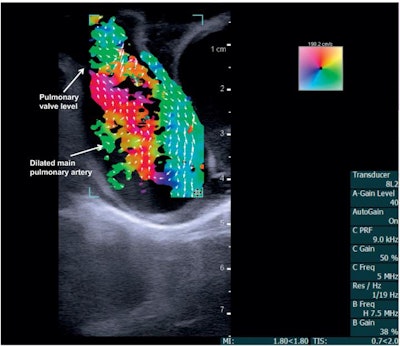

The team used an ultrasound scanner with vector flow imaging to image the hearts of two three-month-old babies, one with a healthy heart and one with congenital heart disease. The technology allowed for complete transthoracic imaging of tissue and blood flow at a depth of 6.5 cm; abnormal flow and cardiac anomalies were clearly visualized in the child with congenital heart disease.

"Vector flow imaging technology is not yet possible in adults, but we have demonstrated that it is feasible in pediatric patients," Jensen said in a statement released by the university April 3. "Our group demonstrated that this commercially available technology can be used as a bedside imaging method, providing advanced detail of blood flow patterns within cardiac chambers, across valves, and in the great arteries."